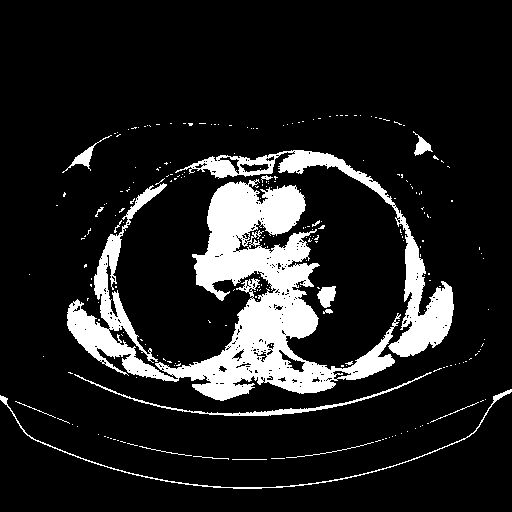

Original NATIVE CT scan (input)

Full window (WL 1023.5, WW 4095 β†’ Low βˆ’1024, High +3071)

Actual HU range: [-1024.0, 3071.0]